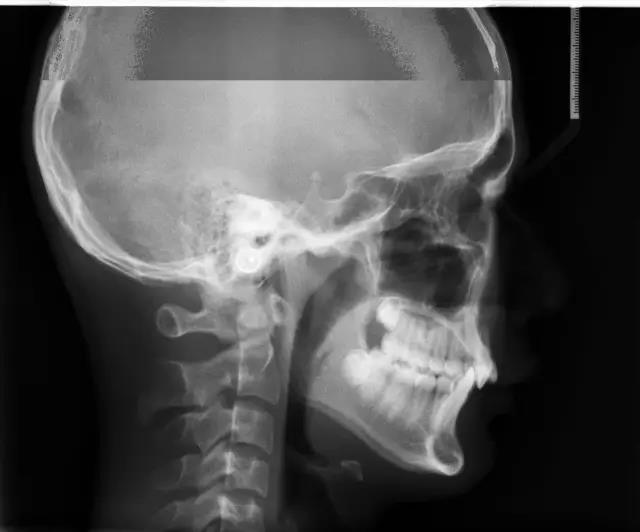

X线头型测量片

让医生了解到牙颌颅面的发育情况,将诊断从表面观察,深入到对整个骨骼的判断。做到精准定位、测量、制定矫治计划。